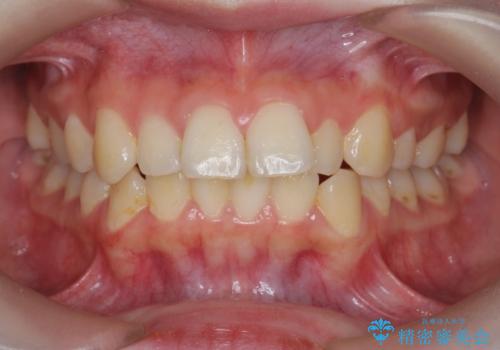

セラミッククラウンによる奥歯の修復

担当医 河口智英